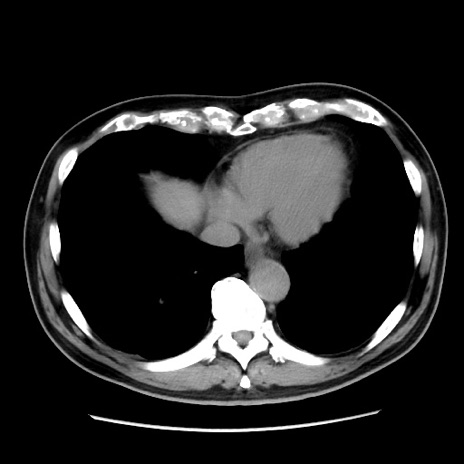

症例16(横断像)

【症例】 70歳代男性

【主訴】 腹痛、嘔吐

【現病歴】 約1ヶ月前より間欠的に腹痛と嘔吐あり、当院消化器内科を受診したところCTで多発する肝臓のLDAを指摘され、精査中であった。以降は消化器症状は安定していたが、2日前より嘔気と腹痛があり、同日より排便・排ガスが消失した。改善認めず、 本日、救急外来を受診した。

【既往歴】 大腸ポリープ切除後。

【身体所見】意識清明・会話良好、BT 36.3℃、BP 127/80mmHg、 P 80bpm、腹部:膨満あり、平坦・軟、上腹部正中および下腹部正中に圧痛あり、反跳痛なし、筋性防御なし。

【データ】WBC 7200、CRP 0.77